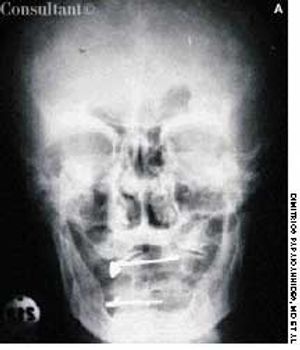

A 74-year-old man, who had been aware of a gradual increase in hat size over the past 3 years, complained of a mild headache and backache. His serum phosphatase level was 1,475 U/L (upper normal limit, 120 U/L). Skull films showed calvarial enlargement caused by thickening of the cortical tables, radiolucency in the frontal and occipital regions, and patchy osteosclerosis that produced a cotton-wool appearance.